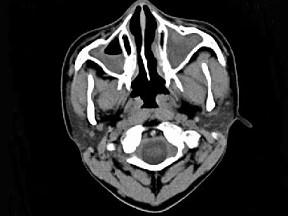

问题 男,14岁,持续性鼻塞、嗅觉减退,流脓涕数年,CT检查如图,最可能的诊断为 ( )

选项 A、恶性肉芽肿 B、上颌窦癌 C、鼻及鼻窦息肉 D、过敏性鼻炎及鼻窦炎 E、鼻炎及鼻窦炎

答案 E